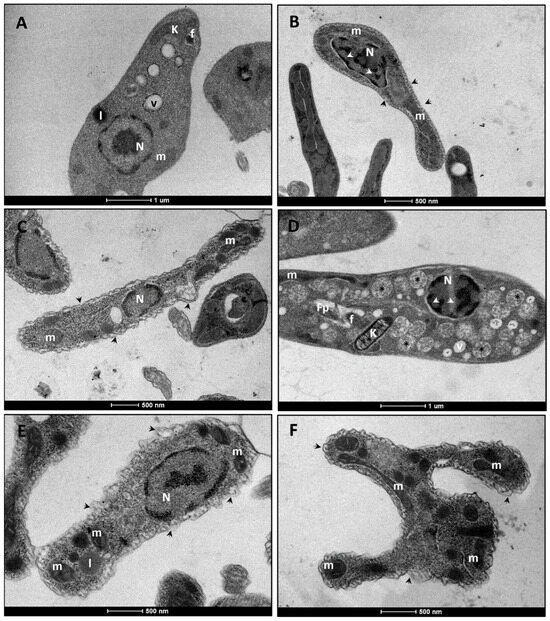

In Vitro and Ultrastructural Evaluation of the Cytotoxic and Antileishmanial Activities of Thiosemicarbazone Compounds Against Promastigotes and Axenic Amastigotes of Leishmania infantum

by Janderson Weydson Lopes Menezes da Silva, Andréa Regina Alves da Rocha Diniz, Alberon Ribeiro de Araújo, Gabriel Gazzoni Araújo Gonçalves, Dyana Leal Veras, Marton Kaique de Andrade Cavalcante, Jana Messias Sandes, Iranildo José da Cruz Filho, Diego Santa Clara Marques, Maria do Carmo Alves de Lima, Ana Paula Sampaio Feitosa, Luiz Carlos Alves and Fábio André Brayner

Trop. Med. Infect. Dis. 2025, 10(11), 325; https://doi.org/10.3390/tropicalmed10110325 - 19 Nov 2025

Leishmaniasis remains a global health challenge, and the search for effective and selective therapeutic agents is crucial. This study evaluated the in vitro antileishmanial and cytotoxic activities of thiosemicarbazone compounds (LT-70, LT-73, LT-75, and LT-89) against Leishmania infantum promastigote and axenic amastigote forms. The compounds demonstrated strong leishmanicidal activity, with IC50 values ranging from 10.5 to 14 µM. At the lowest tested concentration (20 µM) the compounds produced percent inhibitions of 100% (LT-70), 100% (LT-73), 100% (LT-75) and 100% (LT-89). Cytotoxicity assays on J774.A1 macrophages revealed CC50 values from 60 µM to >75 µM, with LT-73 and LT-75 showing low toxicity (CC50 > 75µM). Selectivity index (SI) ranged from 7.1 for LT-75 and 5.8 for LT-73, indicating potential for further development. Ultrastructural analysis by SEM and TEM revealed cellular and organelle damage, including membrane rupture and mitochondrial swelling, especially after LT-73 and LT-75 treatment. Immunomodulatory assays indicated induction of TNF-α and IFN-γ production, with significant IL-6 reduction. Flow cytometry data suggest mitochondrial dysfunction and apoptosis-like features, particularly for LT-73. Membrane potential assays suggested mitochondrial depolarization by LT-73. LT thiosemicarbazone derivatives present specific structural modifications that enhance antileishmanial selectivity and reveal a dual mechanism of action combining mitochondrial dysfunction and immunomodulatory effects. These findings support the potential of thiosemicarbazone derivatives as promising antileishmanial agents with selective cytotoxicity and immunomodulatory effects. Full article